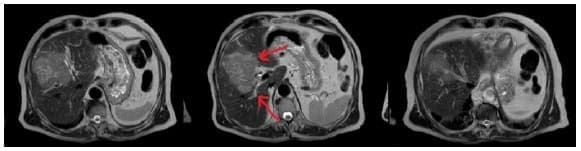

Se realizó RNM de abdomen (figura 4) que reportó compresión extrínseca de la confluencia de los hepáticos, obstrucción y dilatación del ramo biliar hacia el segmento 5, acorde con los hallazgos tomográficos. Y se completó la estadificación mediante TC de cráneo y tórax, y gammagrafía ósea que fueron negativos para extensión metastásica.

Figura 4. Masa hepática de 8 cm en los segmentos 4, 5 y 8. Se muestra el compromiso de la vía biliar hacia el sector lateral izquierdo y del sector posterior derecho (señalado en rojo).

Tras una incisión y abordaje similar al paciente del caso número 1, se disecaron y ligaron las ramas portales izquierdas hacia el segmento 4 por fuera de la cápsula de Glisson a través del espacio de Rex, causando la demarcación isquémica, y también se ligó la rama arterial proveniente de la arteria hepática izquierda (figuras 5 y 6).

Figura 5. Demarcación isquémica del sector anterior derecho (flecha roja – Mesohepatectomía

.

Figura 6. Demarcación isquémica de los sectores centrales: medial izquierdo (flecha verde) y anterior derecho.